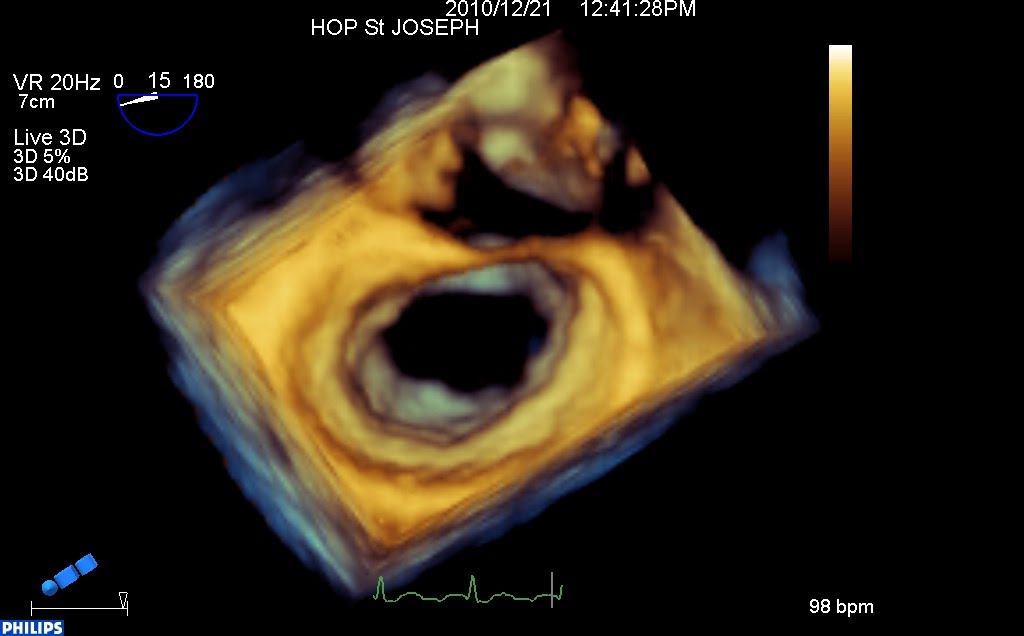

En 3d, (vue « chirurgicale » de l’oreillette gauche habituelle, aorte en haut, auricule à droite) on est d’emblée frappé par la déformation de l’anneau, qui semble aplati sur la commissure antérieure.

Les deux feuillets sont « tractés » vers le ventricule, par le raccourcissement des cordages (le plan de coaptation se situe très en dessous de l’anneau).

La valve ferme au milieu, mais les deux commissures (et surtout l’antérieure) restent ouvertes (et donc fuyantes).

Il s’agit donc d’une fuite rhumatismale, par restriction des deux feuillets, déformation de l’anneau et défaut de coaptation bi-commissurale.

Systole (noter l’absence de coaptation dans les zones commissurales):